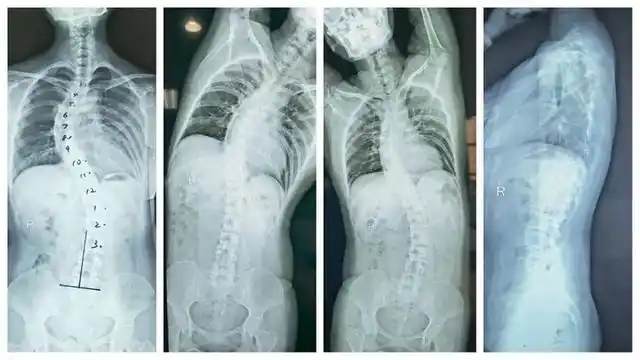

妇幼健康丨你了解自己的脊柱吗怀疑孩子脊柱侧弯x线检查要怎么做

孩子脊柱侧弯严重吗小孩脊柱侧弯严重吗